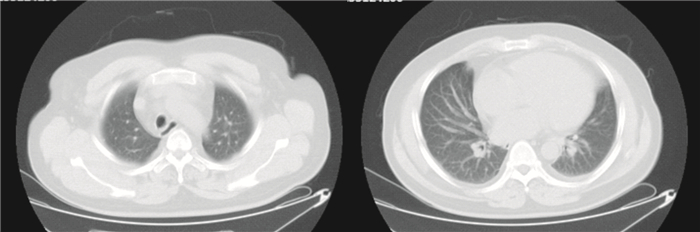

診斷考慮:甲狀腺功能減退癥伴黏液性水腫昏迷、吸入性肺炎、Ⅱ型呼吸衰竭,急性呼吸窘迫綜合征(ARDS)重度。轉入ICU后予以左甲狀腺素鈉片胃管注入,氫化可的松靜滴,哌拉西林舒巴坦抗感染等治療。同時行纖支鏡肺泡灌洗,肺復張,俯臥位通氣等措施;監測血氣、甲狀腺功能、肝腎功能、血常規,調整治療方案。經過積極搶救治療,患者意識逐漸好轉,呼吸性酸中毒糾正,逐漸出現不耐受氣管插管,予以舒芬太尼+右美托咪定鎮痛鎮靜,Ramsay評分維持于3~4分。入ICU后第3 d,胸部CT提示:雙肺大片狀影,心影飽滿(圖 1)。肺動脈血管成像未見明顯異常。第5 d拔出氣管插管序貫為無創呼吸機輔助通氣,第7 d改為鼻導管吸氧3 L/min,指氧飽和度波動于93%~99%,轉出ICU后繼續予以抗感染、補充甲狀腺素(表 1)等治療。復查胸部CT(圖 2),雙肺野尚清,各大氣道通暢,雙側少量胸腔積液。提示肺部感染好轉。住院21 d好轉出院。